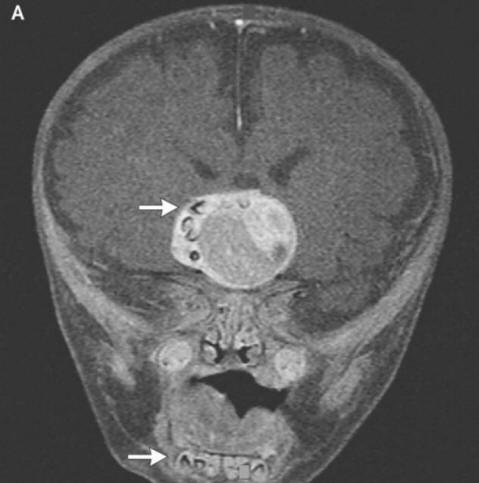

valokuva avoimista lähteistä Kuten kirurgit selittivät pelättyjä vanhempia ja onkologit, tämä johtui harvinaisen synnynnäisen muodostumisesta kasvaimet – craniopharyngiomas, kirjoittaa New England Journal of Medicine. Tämä kasvain valtaosassa tapauksia hyvänlaatuinen voi kuitenkin kasvaa pallon palloksi golf ja aiheuttaa hajua heikentyneen kuulon ja näkökyvyn heikkenemisen, ja lisää myös kallonsisäistä painetta. Tutkijat aina epäili, että nämä kasvaimet, jotka ilmenevät lapsessa jo raskaus, muodostettu samoista soluista kuin hampaat, koska ne havaitsivat suuria kalsiumkerroksia, mutta todellisen muodostuneen hampaan ennen tätä tapausta, jota he eivät löydä kirjanpito

Kirurgit poistivat kuvan onnistuneesti avoimista lähteistä poika, he sanoivat, menee hyvin. Kuitenkin hammas että kasvoi aivolisäkkeessä, mutta häiritsi erityisesti aivoja, asianmukainen hormonien tuotanto – potilaan on otettava ne ennen elämän loppu. Tämä tapaus voi perustellusti olla ylpeä paikasta luettelo onkologien omituimmista toimenpiteistä. Sillä välin, vuonna nuori mies Iranista, joka piti hoita karvaiset silmät. Oudokas kasvain hänen silmässään ilmestyi melkein heti syntymän jälkeen, mutta 19 – vuotiaana se kasvoi huomattavasti vuonna 2006 (enintään 0,6 cm) ja estävät silmäluomien sulkemisen lisäksi siitä jäykät hiukset alkoivat kasvaa. Lääkärit poistivat kasvaimen ja havaitsivat sen tämä on limbaalinen dermoidi – erittäin harvinainen, yleensä hyvänlaatuinen koulutus. Lääkäreiden mukaan siinä tapauksessa jos nuori mies veti edelleen lääkkeillä, hänen turvotuksensa ei vain voinut kasvattaa hiuksia, vaan myös alkaa hikoilla: ajan myötä kasvaimissa vastaavat rauhaset ilmestyvät usein.